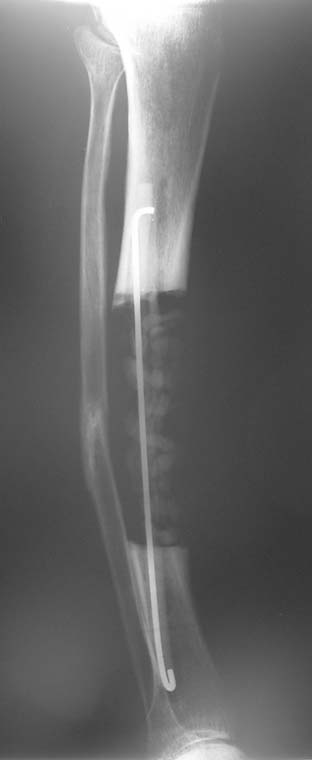

The duration of external fixation (external fixation index) depends on the amount of distraction required, and the extremity is prone to complications during this period. After the distraction phase is completed, the external fixator remains in place during the consolidation phase, which lasts twice as long as the distraction phase; but this period is hardly tolerated. If the external fixator is removed before sufficient consolidation is achieved, fractures, deformity and shortness will be the result. In our department, ‘lenghthening over nail’ method is used in order to decrease the external fixation index and increase patient comfort and activity level. In this method, the intramedullary nail is statically locked after the completion of the distraction phase, and external fixator is removed. The extremity is stabilized by the intramedullary nail during consolidation phase. In this way, complications due to long external fixation index or early removal of the external fixator are avoided.